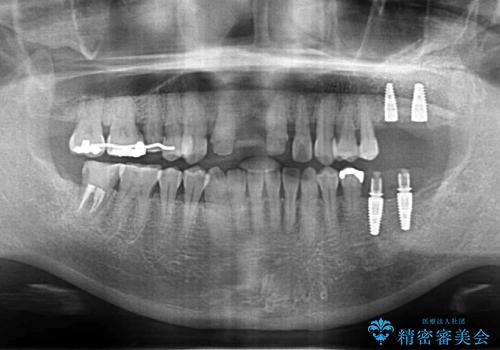

残すことのできない歯は抜去したのち骨造成を含めたインプラント治療を行い、しっかりとした咬合関係を確立していきます。

治療期間はかかりましたが、しっかりと歯周病治療・インプラント治療を行ったおかげで歯周病の状態は非常に良くなり、安定した咬合関係を確立することができました。